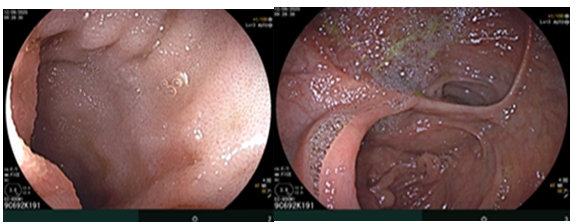

Nội soi đại tràng( thời điểm sau phẫu thuật): Đã phẫu thuật cắt đại tràng phải, nối kiểu tận bên, niêm mạc miệng nối bình thường.

Hình ảnh nội soi đại tràng thời điểm trước phẫu thuật.

Hình 5. Hình ảnh nội soi đại tràng sau phẫu thuật cho thấy niêm mạc miệng nối bình thường.